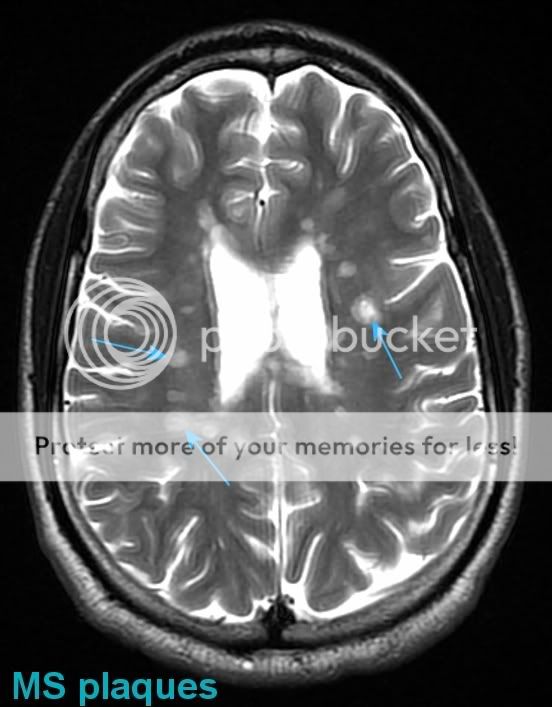

MS MRI Plaque Photo by neurologycoffeecup Photobucket Can You See Plaques And Tangles On Mri Aria refers to imaging findings seen exclusively on mri. The two primary lesions associated with ad are extracellular nonvascular aggregates of aβ (senile plaques) and intraneuronal protein inclusions secondary to aggregation of misfolded and abnormally phosphorylated protein τ (neurofibrillary tangles). Amyloid plaques and tau tangles are believed to be the two molecules responsible for the brain damage associated with alzheimer's. Can You See Plaques And Tangles On Mri.